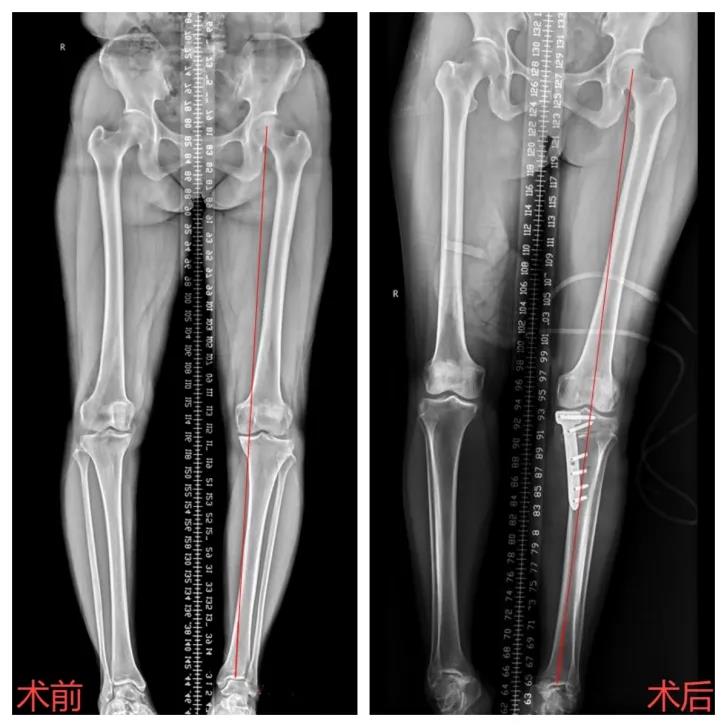

59岁的李阿姨10年前无缘无故出现了左膝关节疼痛不适的症状,负重及长距离行走后疼痛尤为明显,因为休息后疼痛就会有所缓解,所以李阿姨一直都没在意。近1个月来,她的左膝疼痛症状加重,经保守治疗后效果欠佳。到我院膝关节外科就诊,经查膝关节X片显示:1、左膝关节骨性关节炎,2、左膝内翻畸形。科室负责人黄宗权副主任医师带领的保膝团队为其量身定制手术方案,予以行左侧胫骨高位截骨矫形+自体髂骨植骨手术,且手术十分顺利。术后第二天患者即可早期下地部分负重行走。李阿姨在出院时感慨:“之前以为得了膝关节骨性关节炎这个病,只能等着长期的折磨再行关节置换,心理每天非常的焦虑。没想到现在还能通过这种微创手术解决困扰多年的病痛,真值得宣传推广。

胫骨高位截骨术(HTO)是一种经典且常用的早期保膝手术。它针对膝关节内侧间室骨关节炎,通过恢复肢体力线,使膝关节内外侧间室受力重新分布,减少内侧间室受力,促进内侧关节软骨自然修复,缓解膝关节疼痛,恢复膝关节负荷及运动功能。